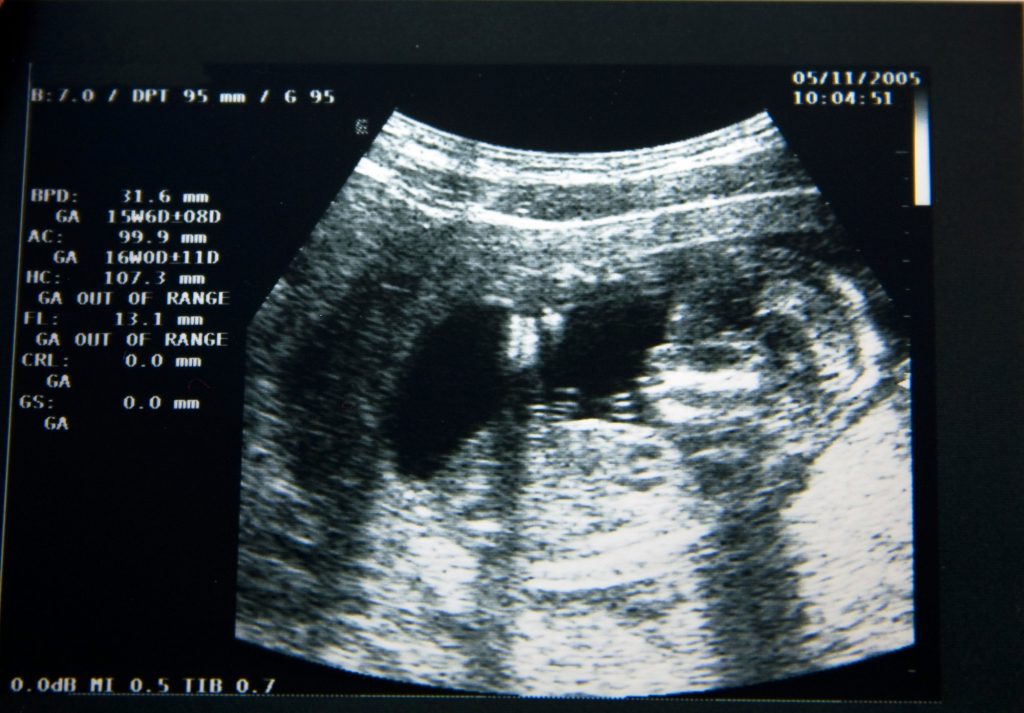

Pe la 15 săptămâni, cu ajutorul ultrasunetelor s-a observat că bebelușii reacționează și se mișcă la un hohot de râs ori la un simplu strănut al mamei. De asemenea, ei memorează vocea mamei și a altor persoane apropiate, pe care le ascultă în mod constant, cum ar fi tatăl sau frații, iar după naștere copilul manifestă vizibil preferințe pentru vocile părinților pe care le-a auzit când era în burtică.